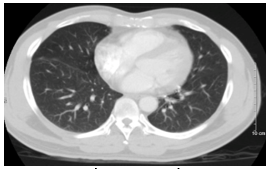

Đến 6 tháng sau bệnh nhân đi khám sức khoẻ được chụp cắt lớp vi tính lồng ngực cho kết quả:Vài nốt đặc thùy giữa và dưới phổi phải, nốt lớn kích thước 10x25mm, tràn dịch màng phổi phải => vào Trung tâm Y học hạt nhân và Ung bướu đánh giá và điều trị

Hình 1: Hình ảnh  cắt lớp vi tính lồng ngực: nốt tổn thương u phổi phải kích thước 10x25mm (mũi tên đỏ), dịch màng phổi phải (mũi tên vàng), tổn thương di căn phổi (mũi tên xanh).